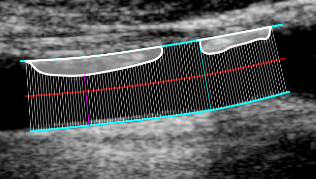

This tool can be used for a quantitative analysis of the plaques. The user has to manually trace the two borders of the vessel, then the border of one or more plaques can be added.

Tracing the borders

• Click the Trace the borders images/download/thumbnails/388694064/cvs_borders_button-version-1-modificationdate-1761815630116-api-v2.png button in the Setup panel.

• Start tracing the first border by clicking on the image.

• Move the mouse and click to add points to the borders.

• Right click to end the tracing of the first border.

• Start tracing the second border by clicking on the image.

• Right click to end the tracing of the second border.